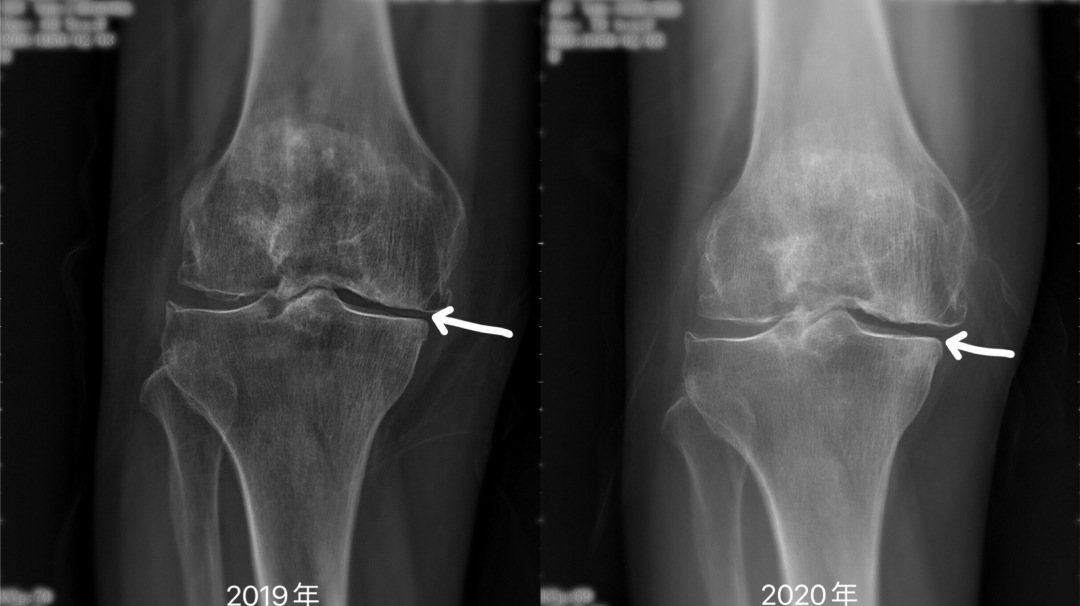

通过PRP结合运动训练的综合治疗,张阿姨的双膝疼痛症状明显改善,VAS评分从治疗前的7-8分降至1-2分。不仅疼痛症状缓解,张阿姨双下肢的运动功能也有明显改善,股四头肌的等速峰力矩值显著提高,步行能力Holden评分也从3分改善至5分正常,上下楼梯、自我沐浴等日常生活活动能力有所改善。在1年后门诊随访时,张阿姨惊喜的发现,相较于治疗前的膝关节X线,她的双膝退变情况有了明显好转。

PRP注射治疗1年前后患者膝关节间隙改变